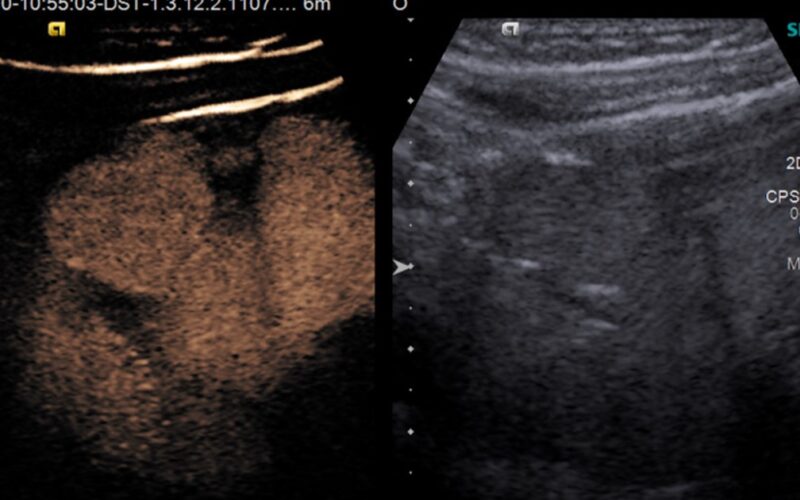

Ultrazvučna kontrastna mikciona urografija – cistografija (CeVus) je visoko osetljiv dijagnostički postupak u otkrivanju veziokoureteralnog refluksa, koji je u dečijem uzrastu najčešći uzrok ponovljenih urinarnih infekcija.

Ova metoda koristi ultrazvučno kontrastno sredstvo koje se direktno kateterskom tehnikom plasira u mokraćnu bešiku i na taj način omogućava praćenje kontrastnog sredstva, BEZ primene jonizujućeg zračenja.